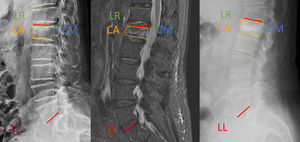

Before starting surgery, the fracture level was located and marked using fluoroscope, together with the position of the pedicles. The trocar was introduced into the vertebra using the “battleships” technique (Fig. 1): each half of the vertebral body was divided into four parts. In the anteroposterior projection, five vertical lines were drawn (lateral edge of the body; lateral edge of the pedicle; middle of the pedicle; medial edge of the pedicle and spinous process). Once half of the vertebral body was divided into four areas with five lines, they were named with the letters A (lateral edge of the body-lateral edge of the pedicle), B (lateral edge of the pedicle-middle of the pedicle), C (middle of the pedicle-medial edge of the pedicle) and D (medial edge of the pedicle-spinatus).

In the same way, five vertical lines were drawn in the lateral projection: posterior edge of the joint, posterior edge of the pedicle, midpoint of the pedicle, anterior edge of the pedicle and anterior edge of the vertebral body. Four areas were marked, which we called 1 (posterior edge of the joint-posterior edge of the pedicle), 2 (posterior edge of the pedicle-middle of the pedicle), 3 (middle of the pedicle-anterior edge of the pedicle) and 4 (anterior edge of the pedicle-anterior edge of the vertebral body).

Using this terminology, we designated the location of the trocar tip with a letter in the anteroposterior projection and a number in the lateral projection.

With “battleships” in mind we are able to make a 5×5 table, in which we place the anteroposterior areas in the first row and the lateral areas in the first column. To understand which positions correspond to each quadrant, we can place an image of a coronal section of the vertebra as follows: the combination of both characters will give us three possible results, pedicle: A1, B2, C3 and D4; lateral: A2, A3, A4, B3, B4, C4, and medial: B1, C1, C2, D1, D2, and D3. With this simple coordinate method, using two anteroposterior and lateral images, we can locate the tip of the trocar at any time during minimally fluoroscopically assisted pedicle canalisation.

The radiological analysis included preoperative imaging tests (plain X-rays in anteroposterior and lateral projections and nuclear magnetic resonance [NMR], and postoperative (plain X-rays in anteroposterior and lateral projections on the first postoperative day and standing radiographs or teleradiographs during follow-up). The measurements taken on the preoperative and postoperative radiological images were: anterior spinal height (AC), posterior spinal height (PC), fractured vertebral kyphosis (FVK): measurement of the angle formed between the vertebral endplates, regional lordosis (RL): measurement of the angle formed between the upper endplates of the proximal vertebra and the lower endplate of the distal vertebra, lumbar lordosis (LL): angle formed between the upper endplate of L1 and the lower endplate of L5 (Fig. 2).